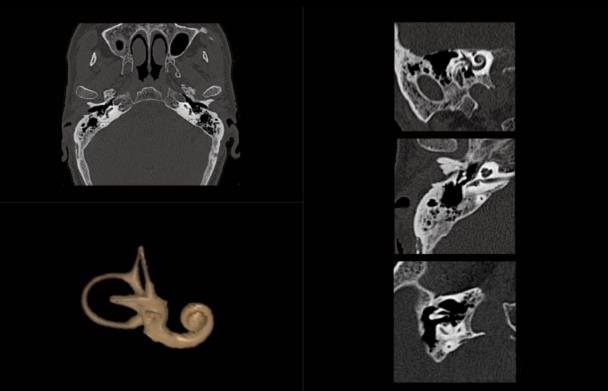

8、内耳CT成像:

耳部ct可以显示外耳道的前、后壁,鼓膜,鼓室,听小骨组成的听骨链,前庭窗,耳蜗,半规管和前庭,前庭水管,内耳道。